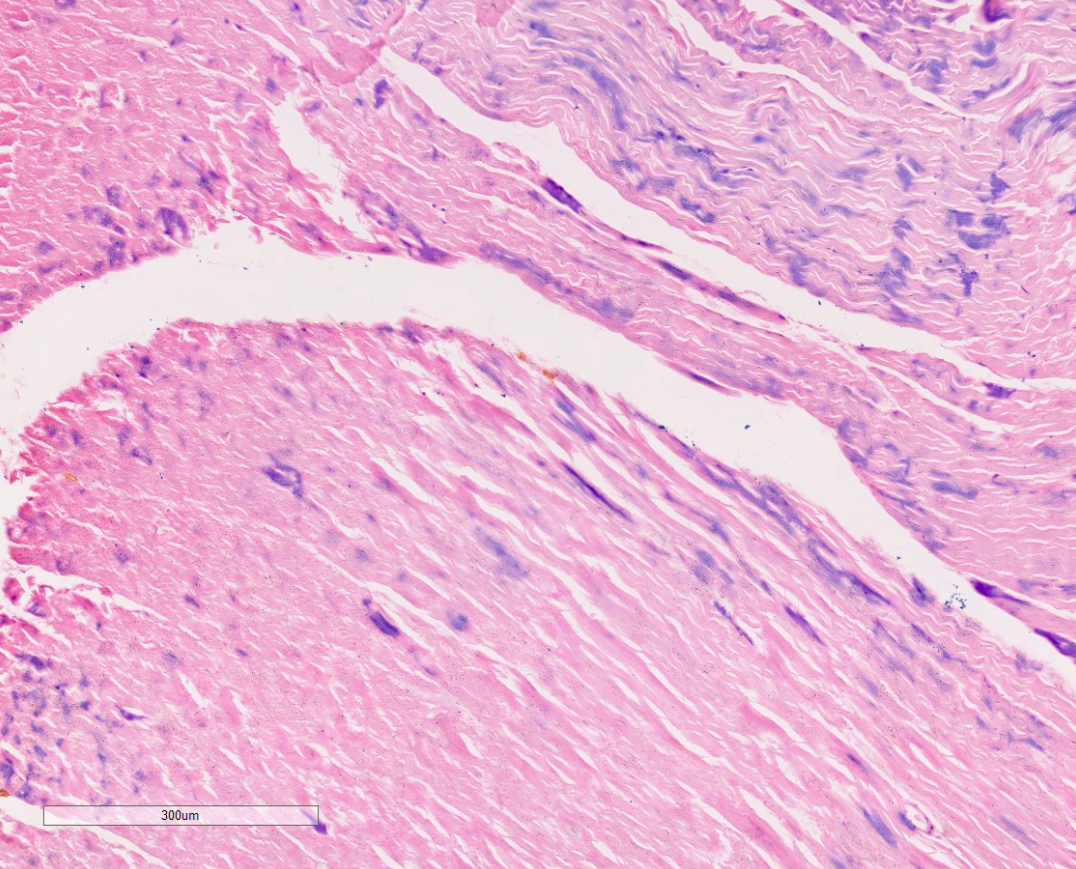

1、HE染色实验结果(小鼠肝脏-肺脏-心肌举例)

HE实验结果解读:细胞核呈现蓝色或者紫蓝色,细胞质和细胞外基质中的成分着红色。